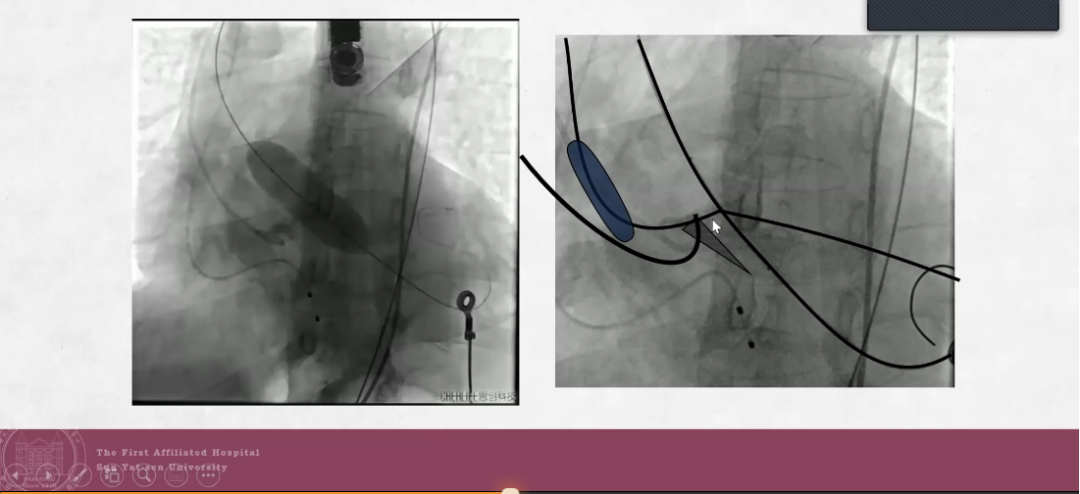

综合患者病例特点,手术方案初步拟定为球囊预扩后植入瓣膜。术中主动脉根部造影发现心脏显著横位,瓣口钙化部位无随收缩运动,合并部分返流。由于钙化位置存在锋利成角,20mm预扩球囊无法顺利跨瓣,遂更换支撑力更好的导丝及更小的18mm球囊,在球囊轻度充盈状态下顺利跨瓣,先后进行6次预扩。最末次预扩时,可见钙化被完全推开,但预扩球囊破裂,且球囊回撤时与导丝缠绕,卡在外鞘无法完全回撤。最终经外科手术切开股动脉并将其取出,再次进行球囊预扩(25mm),顺利植入S3瓣膜。